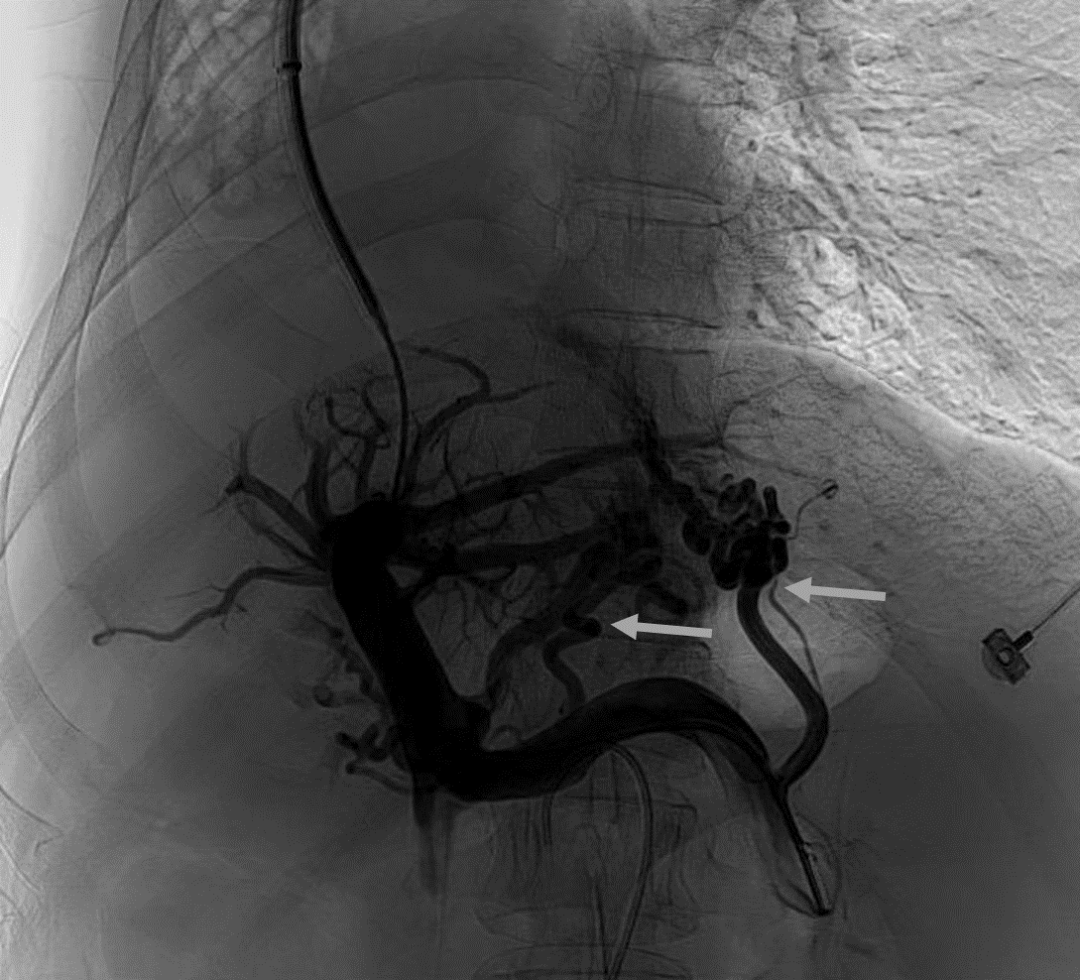

韓國宏教授介紹,TIPS手術(shù)是通過在肝靜脈與門靜脈之間的肝實質(zhì)內(nèi)建立分流通道,通過降低門靜脈壓力來預(yù)防和治療因門靜脈高壓引起的食管胃底曲張靜脈破裂出血或頑固性腹水。該手術(shù)不用開刀、創(chuàng)傷小、操作過程復(fù)雜、技術(shù)難度大、安全風(fēng)險高,是目前外周血管介入中難度最大的手術(shù)之一。再加上人群中右位心發(fā)病率極低(約萬分之一),經(jīng)查閱文獻,在國內(nèi)外尚未有類似病例報道,無經(jīng)驗參考。在右位心基礎(chǔ)上行TIPS術(shù),無疑是難上加難。我們反復(fù)研究患者肝臟及心血管的特殊情況,詳細(xì)討論了手術(shù)方案,決定放棄常規(guī)的肝靜脈穿刺,另辟蹊徑,選擇高難度高風(fēng)險的肝后段下腔靜脈穿刺門靜脈左支,憑借多年的經(jīng)驗和嫻熟的技術(shù)最終成功的在下腔靜脈與門靜脈之間放置了TIPS專用支架,術(shù)后門靜脈壓力梯度從術(shù)前的19mmHg降至3mmHg,曲張靜脈消失,解決了困擾曹女士多年上消化道出血的困擾。患者術(shù)后第二天即可正常下床活動。